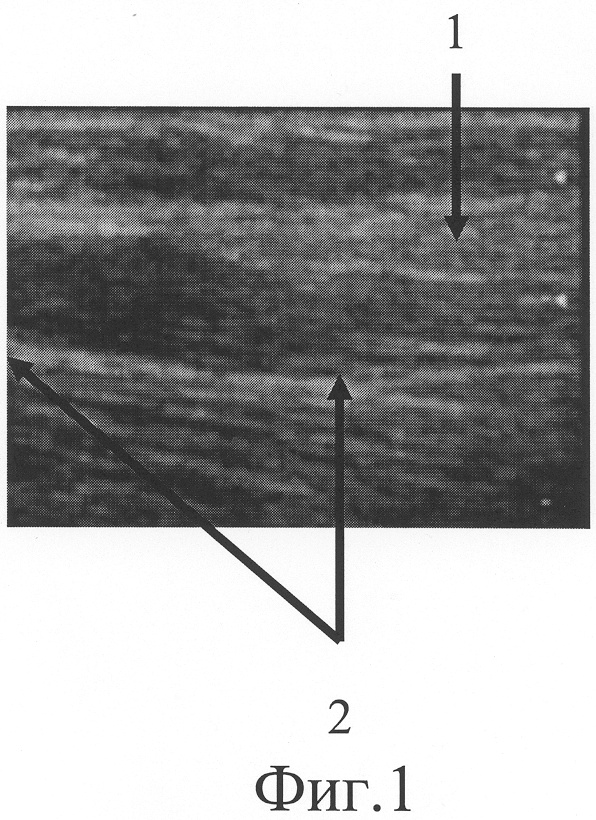

На фиг.1 представлена сонограмма больной А., 52 лет, с застарелым повреждением локтевого нерва в средней трети правого предплечья (проксимальный фрагмент локтевого нерва).

При ультрасонографическом исследовании (фиг.1) установлено, что проксимальный фрагмент локтевого нерва (фиг.1-1) прерывается в средней трети предплечья, на его конце располагается неврома, линейный размер которой составляет 16 мм (фиг.1-2). Дистальный фрагмент нерва, обнаруженный на границе средней и нижней трети предплечья (фиг.2-5), патологически измененен на протяжении 17 мм (фиг.2-4) На сонограмме (фиг.3) визуализируется область диастаза. Диастаз между невромой и дистальным фрагментом равен 77 мм. Размер участка срединного нерва, подлежащего возмещению, составляет сумму линейного размера невромы проксимального фрагмента по линии продольной оси нервного ствола, протяженности диастаза между невромой и дистальным фрагментом, линейного размера патологически изменененного дистального фрагмента и равен 110 мм.